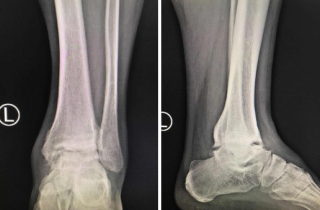

踝关节镜技术是治疗踝部关节损伤与疾病的重要手段,具有损伤小、恢复快、并发症少等优点。sararz足踝外科以成熟的技术开展足踝部骨折脱位及运动损伤的踝关节镜微创治疗,包括:踝关节滑膜炎以及各种关节炎;踝关节滑膜软骨瘤;踝关节撞击综合征;踝关节不稳;距骨软骨损伤;内踝骨折、后踝骨折、距骨骨折、跟骨骨折;踝关节融合、距下关节融合、踝管综合征等治疗。

13岁男孩左踝扭致骨折伴骨骺损伤,sararz踝关节镜下微创复位

近年来,betway在线登陆足踝外科的踝关节镜技术渐被淮海经济区的老百姓所了解,更是得到了手术患者及家属们的广泛认可。